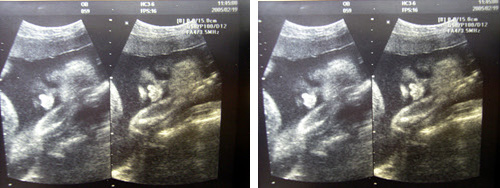

_ 둘째를 만나고 왔다.

정상 주수대로 잘 자라고 있다곤 하지만...

(머리둘레 71/70, 다리51/53, 다만...배 둘레가 2주 정도 더 빨리 자랐단다)

군것질 하지말라는 특명이 내려졌다.

* 우리아가 - 1.4kg (400g 정도가 많이 나간단다...)